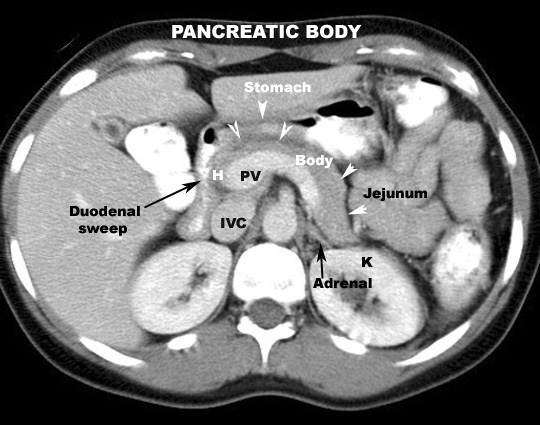

- Body

- Anterior

- Stomach separated by omental bursa

- Posterior

- Aorta

- SMA

- Left crus of diaphragm

- Left adrenal

- Left kidney

- Left renal vein

- Splenic vein

- Inferior

- Transverse mesocolon

- Duodeno-jejunal junction

- Left colic flexure